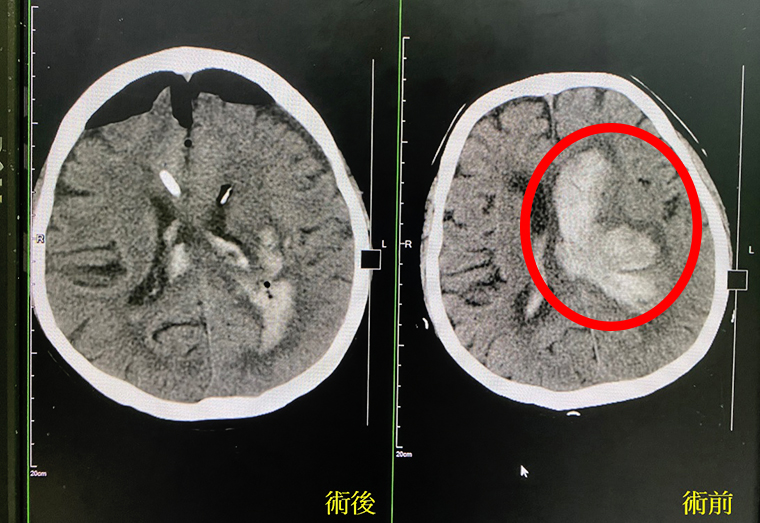

▲電腦斷層照,右圖紅圈處為血塊、左圖為術後照。(圖/長安醫院提供)

朱彥澤說明,腦部電腦斷層掃瞄報告顯示,個案左腦有腦出血,導致阻塞性水腦症狀,並合併急性意識障礙,緊急執行內視鏡腦出血手術,清除大部分血塊,至於深層血水則透過引流管慢慢引流。

近年內視鏡手術進步,利用高清內視鏡進入腦室,反覆抽吸清除血塊,並以單極電燒方式止血,順利地清除大部份的血塊都清掉了,至於更深層的血水,則透過引流管慢慢引流,減少對於腦部組織的損傷。